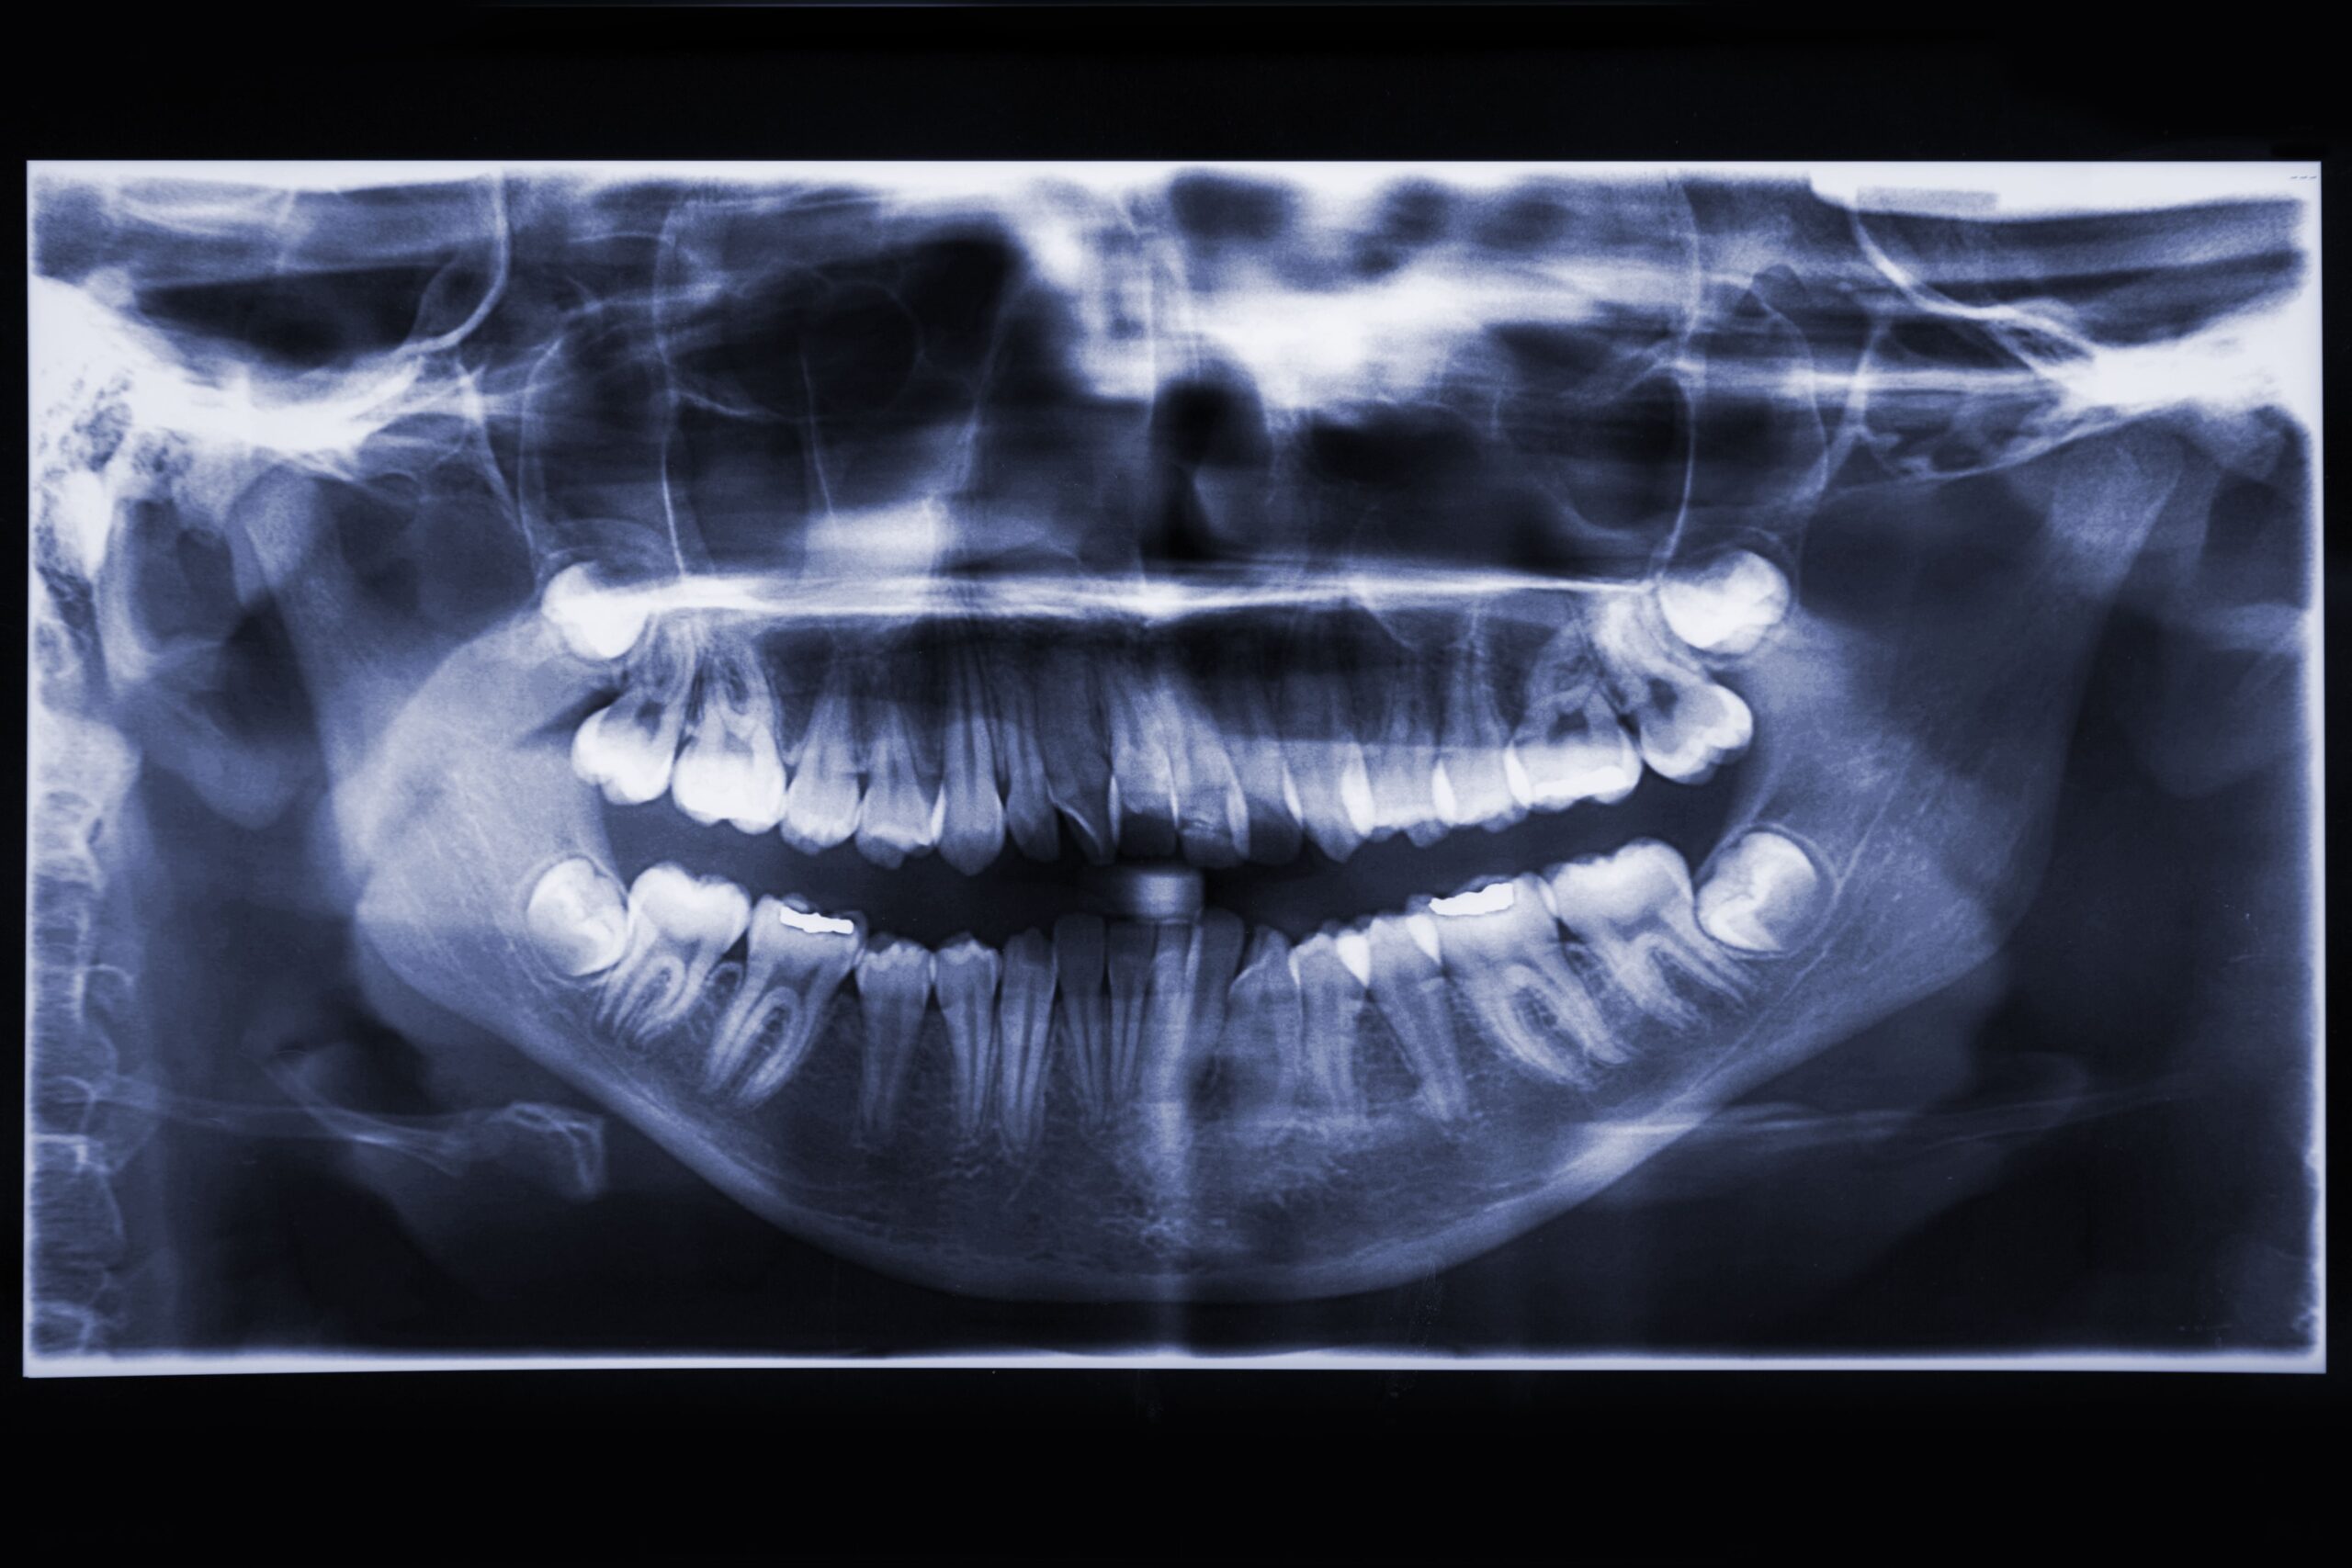

Fillings

Dental fillings restore teeth damaged by decay or fractures. Modern filling materials offer durable, natural-looking results, including tooth-colored composite resins and advanced cementable materials. These options provide strong, effective restorations while preserving the appearance and function of your natural teeth.

Root Canal

Root canal therapy treats teeth with inflamed or infected pulp caused by deep decay, cracks, or repeated dental procedures. This treatment removes infection, relieves pain, and preserves the natural tooth. With proper care, a treated tooth can function normally for many years.

Oral Surgery

Wisdom teeth are the last molars to erupt and often lack enough space to grow properly. Impacted wisdom teeth can cause pain, swelling, decay, gum disease, and damage to nearby teeth. Early evaluation and removal help prevent complications and protect long-term oral health.